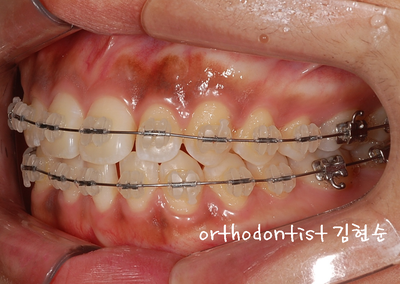

- 치열 벌어짐 -

- 교정 문의 환자 : 추 0 0

- 나이 : 26 세 F 학생

- 교정 사유 : 치열 벌어짐 / 앞니 공간

- 치아 사이사이 공간 벌어지고 치아 심선도 맞지 않습니다,

- 상 / 하 치아 벌어짐을 보실 수 있습니다 아래쪽이 더 벌어짐이 심해 보입니다

- 오른쪽 옆모습 벌어진 모습을 확인할 수 있습니다